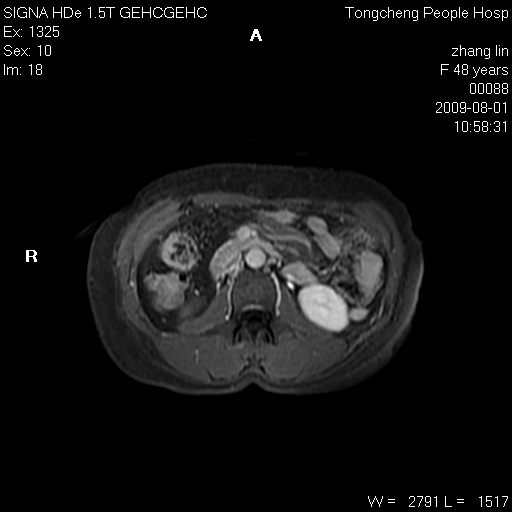

右肾上极见一类圆形病灶,t1wi呈等信号t2wi呈等高混杂信号,三期增强无强化,边界清---考虑囊肿出血。

同反相位均表现为等信号,病变无强化,考虑含蛋白的囊肿可能,弥散加权相或许有些帮助,

肝囊肿

慢性胆囊炎